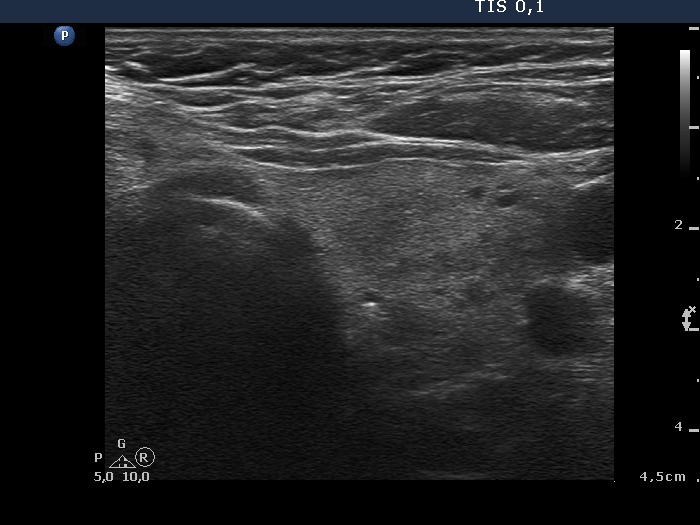

100 consecutive patients with thyroid nodule - Case 26.

8 months after sclerotherapy (ultrasonographic picture 4)

Left lobe, horizontal scan. This lobe has not changed.